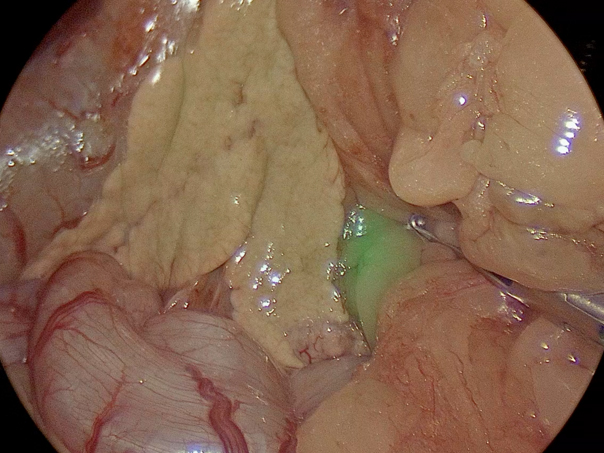

手術の様子

腹腔鏡カメラを用いて膵臓の確認、ICGを用いての膵臓腫瘤の辺縁の確認